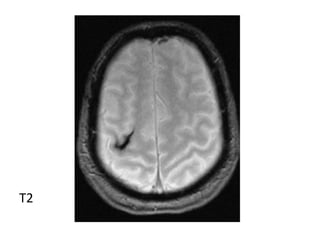

Hyperacute Infarct

T1

T2